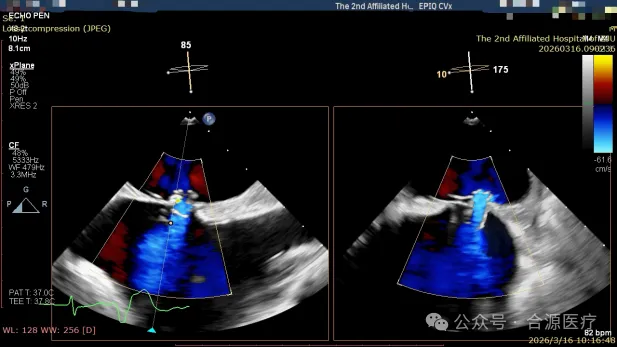

植入后即刻超声心动图评估

手术过程由心脏内科、超声科、麻醉科组成的多学科团队紧密协作开展,患者在全麻状态下,经右侧股静脉成功穿刺,建立介入通路。术者在经食道超声心动图(TEE)的实时动态引导下,于卵圆窝处成功完成房间隔穿刺,将鞘管送入左心房。随后,输送系统将NOVAtria™沿导丝送入左心房。在超声与X射线的双重引导下,术者精细调整输送导管的方向与角度,将植入物稳稳定位于房间隔理想位置。术后经超声多切面扫描确认,器械位置正确,形态完整,分流通畅。